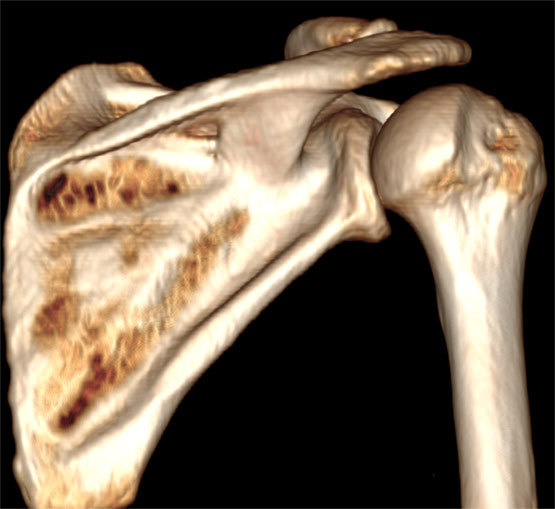

Reconstrucțiile se fac preferabil din secvențele cu fine (kernel de părți moi). Cele reconstruite din imaginile cu kernel de os sunt cu margini prea ascuțite.

Image

Reconstrucție tridimensională a oaselor din articulația umărului (VRT) din imaginile cu kernel de os - contururi sharp

În cazurile în care zona de interes este acoperită de alte structuri, imaginea se prelucrează software, eliminând din imagine părțile care nu sunt utile. Exemplu: eliminarea din imagine a humerului, pentru a permite vizualizarea cavității glenoide.

Aspect de rotație în jurul axului după "decuparea" din imagine a humerusului, pentru o mai bună vizualizare a cavității glenei scapulei.